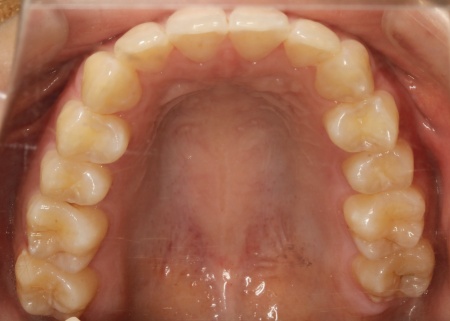

治療前